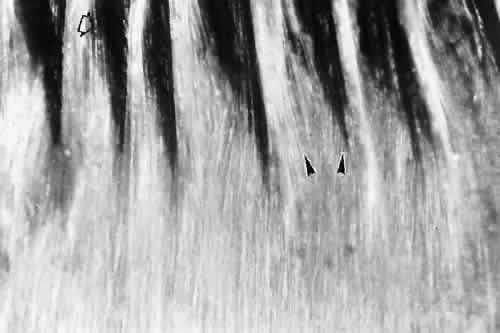

Zonular fibers are first seen at the end of the third fetal month, lying within the secondary vitreous at its base and passing through the matrix of the tunica vasculosa lentis to attach to the lens capsule.2 The mechanisms and factors guiding their highly oriented and predictable attachment to sites on the lens capsule are still unknown. In late fetal life the adult pattern is already apparent, with silvery zonular fibers passing over the tops of the low ciliary processes while others dip into the valleys between the processes, and some change direction by running up along the sides of the processes (Fig. 2). The primary candidate for synthesis of the zonule is the ciliary nonpigmented epithelium. Autoradiographic studies on fetal and young mammalian eyes showed an early accumulation of labeled carbohydrate components and amino acids including cys-teine (present in high concentration in the zonule)on zonular fibrils close to the epithelium of the pars plana and posterior pars plicata.3,4 This proximity suggests that new protein is added at the ciliary end of the zonule and that the ciliary nonpigmented epithelium is its source. In culture, these cells as well as lens and ciliary pigment epithelial cells are capable of producing fibrillin microfibrils,5,6 as do many basement membrane-secreting epithelial cells. By in situ hybridization, the ciliary nonpigmented epithelium of the fetal mouse is indeed positive for fibrillin-1, the main protein of zonular and other elastic system microfibrils.7 However, the lens epithelium in the metabolically most active equatorial region has some fibrillin-1 positivity at the same developmental stages and may contribute as well to the early zonule.8 It is not known whether zonular synthesis is continuous postnatally through at least the most active period of ocular growth, or whether a continuous low-grade renewal process occurs.

Fig. 2. Silvery layer of delicate zonular fibers lies over the pars plana and low processes of the infantile eye. Some fibers pass over the tops of the processes (open arrow), some deep into the valleys, others higher on the sides of the processes (arrowheads) (unstained, × 45).